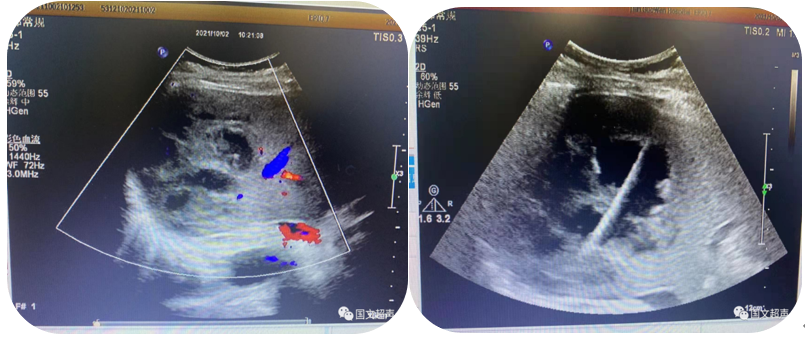

1.超聲引導(dǎo)下穿刺活檢

超聲的實時引導(dǎo)下,穿刺針插入腫大淋巴結(jié)、疑似占位等特定部位進行組織抽吸、切割獲取病理標(biāo)本幫助疾病診斷。

超聲引導(dǎo)下淺表淋巴結(jié)穿刺活檢